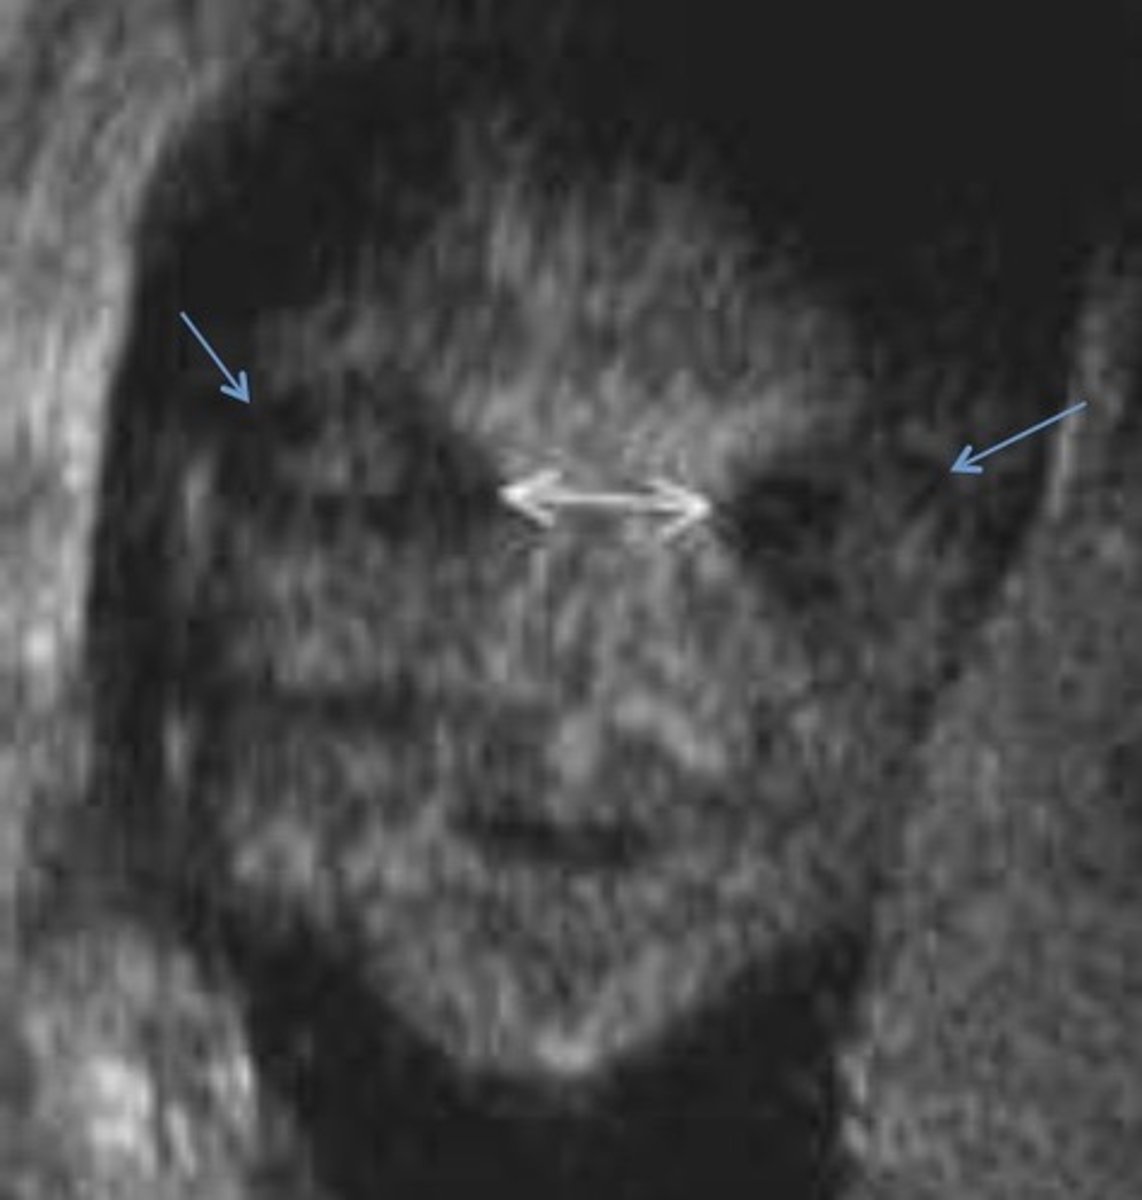

Midface Dysplasia

Jaw and cheekbones do not grow well

Depressed or absent nasal bridge

Eyes and forehead appearing to bulge

Hypertelorism

Wide spread eyes

Common with frontal cephalocele

Hypotelorism

Decreased spaced between eyes

Common with skull/brain anomalies & syndromes